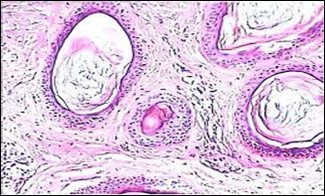

A cogent tissue specimen demonstrates typical features of comedones as follicular ostia distended and impacted with keratin. Significant histological manifestations are the occurrence of enlarged, grouped, distended follicular ostia demonstrating an absence of hair shafts along with impaction of laminated keratin. Base of the follicular invaginations may or may not delineate singular, rudimentary glandular structures. Miniature cysts, cystic invaginations and occasional enlarged cysts can be encountered. Cystic articulations are diverse and preponderantly layered by keratinizing, stratified squamous epithelium. Hyperkeratosis or epidermolytic hyperkeratosis and acanthosis of superimposed epidermis can concur although the lesion is devoid of parakeratosis or dyskeratosis5, 6.

Nevus comedonicus demonstrates immune reactivity to cytokeratin, simulating the expression of normal cutaneous surfaces. Generally encountered within the granular epidermal layer, immune reactivity for filaggrin is demonstrable within the entire epidermal thickness of closed comedones, a molecular which can be implicated in the genesis of nevus comedonicus6, 7. Electron microscopy demonstrates an enhanced quantification of Langerhans cells, numerous kerato-hyaline granules along with an abundance of tonofilaments within upper portion of stratum spinosum. Incompletely differentiated arrector pili muscles are impacted with intracellular glycogen particles6, 7. Figure 1, Figure 2, Figure 3, Figure 4, Figure 5, Figure 6, Figure 7, Figure 8, Figure 9, Figure 10.

Figure 1.Nevus comedonicus with grouped, dilated follicular ostia, impacted with keratin and a layering of hyperkeratotic stratified squamous epithelium11.

Figure 2.Nevus comedonicus with plugging of follicular ostia, keratinous impaction and a lining of hyperkeratotic stratified squamous epithelium11.